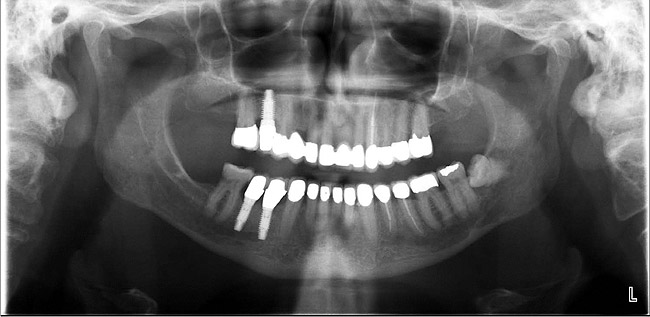

Figure 13  Radiograph depicting the necessity of horizontal placement parameters to prevent vertical defects from becoming horizontal defects.

Figure 13